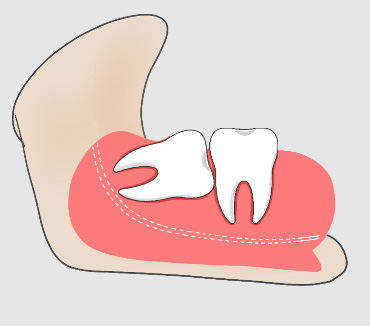

什么是阻生智齿?

阻生牙是指部分萌出或完全不能萌出,且以后也不会自行萌出的牙,这种萌出异常是由邻牙、骨或软组织的阻碍引起的。其中阻生第三磨牙也叫做阻生智齿。

什么是侵犯邻牙?

智齿萌发的空间不足,倒在第二大臼齿上。通常患者不自知,而由牙医以X光诊断得知。

智齿侵犯邻牙的危害

智齿如果一直朝着挤压邻牙的方向生长,就会导致邻牙破坏、牙根吸收,最终两颗牙齿都保不住。